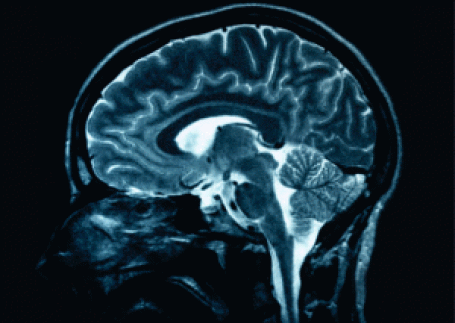

Neuroplasticity is the innate ability of the brain to physically change when challenged with new experiences (Bear, Conners, & Paradisco, 2007).

The brain has over a billion neurons - its cellular building blocks interact with each other in complex ways. Signals travel from one neuron to another down intricate neural pathways whose structures determine your thoughts, emotions, insights and more. As our brain ages throughout life, changes occur. In fact, less-used neural pathways are ‘pruned away’, while frequently used neurons grow stronger (Bowden, Woodbury, & Duncan, 2013).

Even before a child is born, the brain is developing along a predetermined path. This linear, stepwise process continues on until the child reaches full brain maturity in their late teens or early twenties. Although this is an innate process, it is influenced strongly by the environment (Fong, Lee, & Pang, 2011). Therefore, neuroplasticity is a very critical quality of brain health, reshaping new and existing neural pathways.